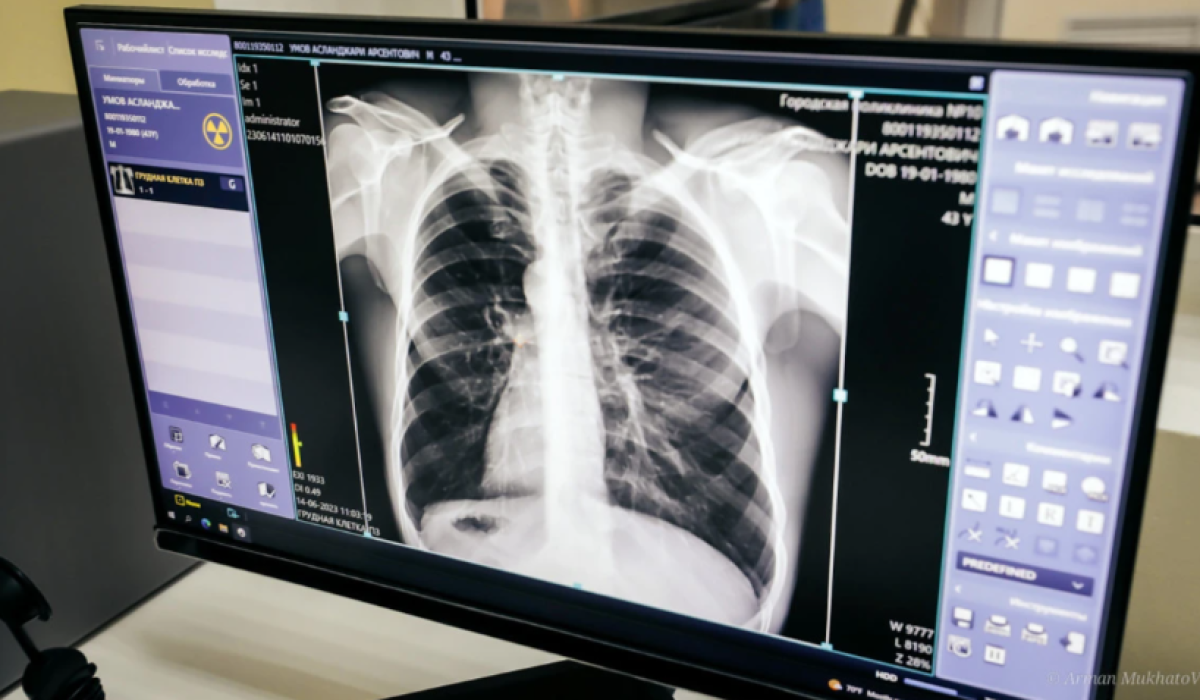

Атырау облыстық денсаулық сақтау басқармасының баспасөз қызметінен мәлім еткендей, науқасқа «Екі өкпенің инфильтративті туберкулезі, ыдырау сатысы» деген диагноз қойылған.

Науқас өкпе туберкулезімен 1992 жылы сырқаттанып, емделген. 1992 жылы оң жақ өкпесінің жоғарғы бөлігіне резекция операциясы жасалған. Емдеудің нәтижесінде сырқатынан сауығып шыққан, - деп хабарлады басқарманың баспасөз қызметі.